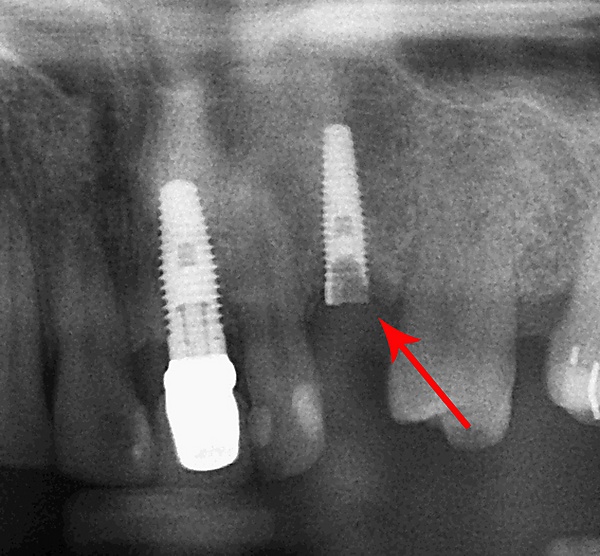

В дальнейшем обязателен ежегодный осмотр специалистом, в процессе которого:

- с помощью рентгенографии изучаются качество и плотность костной ткани;

Разборный имплантат состоит из непосредственно имплантата и надстройки (супраструктуры), именуемой абатментом. Такой имплантат может быть установлен по одно- и двухэтапному протоколу. Двухэтапный протокол подразумевает полное погружение имплантата и накрывание его слизистой оболочкой, в результате чего исключается любой контакт имплантата с полостью рта — эта процедура называется первым этапом дентальной имплантации. Второй этап заключается в установке какой-либо надстройки (супраструктуры) — это может быть как формирователь десны, так и абатмент с временной коронкой или другим видом протезной конструкции. После какого промежутка времени будет выполнен второй этап обычно решает имплантолог, опираясь на данные о качестве костной ткани, возраст и общее состояние пациента, а также свой клинический опыт. Классические сроки составляют 4—6 месяцев, однако последнее время существует тенденция к сокращению сроков ожидания до 2,5—3 месяцев. Это связано с лучшим пониманием процесса остеоинтеграции, а также оптимизацией макродизайна и микрохарактеристик поверхности имплантатов.

Внутрикостные имплантаты по форме разделяют на корневидные, пластиночные и комбинированные. Наибольшее распространение имеют корневидные имплантаты, которые могут быть цилиндрической или конической формы.